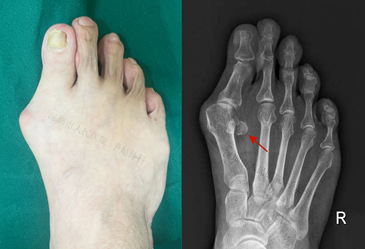

图3:拇外翻患者往往伴有籽骨半脱位和脱位(箭头)

拇趾籽骨半脱位和脱位常见于中、重度拇外翻畸形的患者。随着拇外翻畸形程度的加重,止于近节趾骨基底以及外侧籽骨的收肌联合肌腱会导致拇趾旋前,当拇趾外翻移位时,第1跖骨会出现内收,籽骨与第2骨趋于保持正常的位置关系,第1跖骨与籽骨关节会出现半脱位或脱位。

随着籽骨脱位的发展,与其解除的骨间嵴会发生磨损。轻、中度拇外翻患者的轴位片可显示籽骨间嵴,有一定程度的变平,而重度患者骨间嵴可能消失。籽骨间嵴的过度磨损也会导致籽骨关节面的磨损,导致跖籽关节炎,引起疼痛。